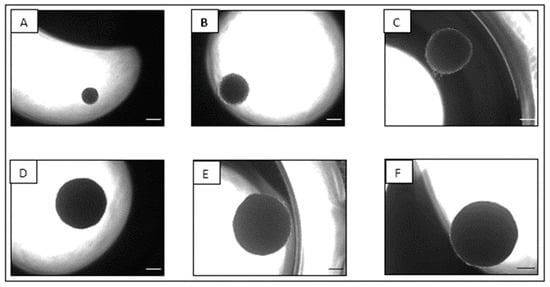

2.2. Spheroid Formation and Maintenance

2.3. Characterization of the NCI-H69AR Spheroid Model

2.3.1. Planimetry